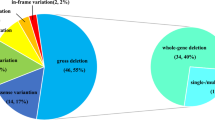

Age range of patients included in this study was 3 months to 6 years and all patients showed hypokalemic metabolic alkalosis. 3 patients additionally displayed hypercalciuria, with evidence of nephrocalcinosis in one case. Screening by Whole Exome Sequencing (WES) and long range PCR revealed that 12/17 patients (70%) had a deletion of the entire CLCNKB gene that was previously identified as the most common cause of Bartter Syndrome in other populations. 4/17 individuals (approximately 25% of cases) were found to suffer in fact from pseudo-Bartter syndrome resulting from congenital chloride diarrhea due to a novel homozygous mutation in the SLC26A3 gene, Pendred syndrome due to a known homozygous mutation in SLC26A4, Cystic Fibrosis (CF) due to a novel mutation in CFTR and apparent mineralocorticoid excess syndrome due to a novel homozygous loss of function mutation in HSD11B2 gene. 1 case (5%) remained unsolved.

Our findings demonstrate deletion of CLCNKB is the most common cause of Bartter syndrome in Iranian patients and we show that age of onset of clinical symptoms as well as clinical features amongst those patients are variable. Further, using WES we were able to prove that nearly 1/4 patients in fact suffered from Pseudo-Bartter Syndrome, reversing the initial clinical diagnosis with important impact on the subsequent treatment and clinical follow up pathway. Finally, we propose an algorithm for clinical differential diagnosis of Bartter Syndrome.